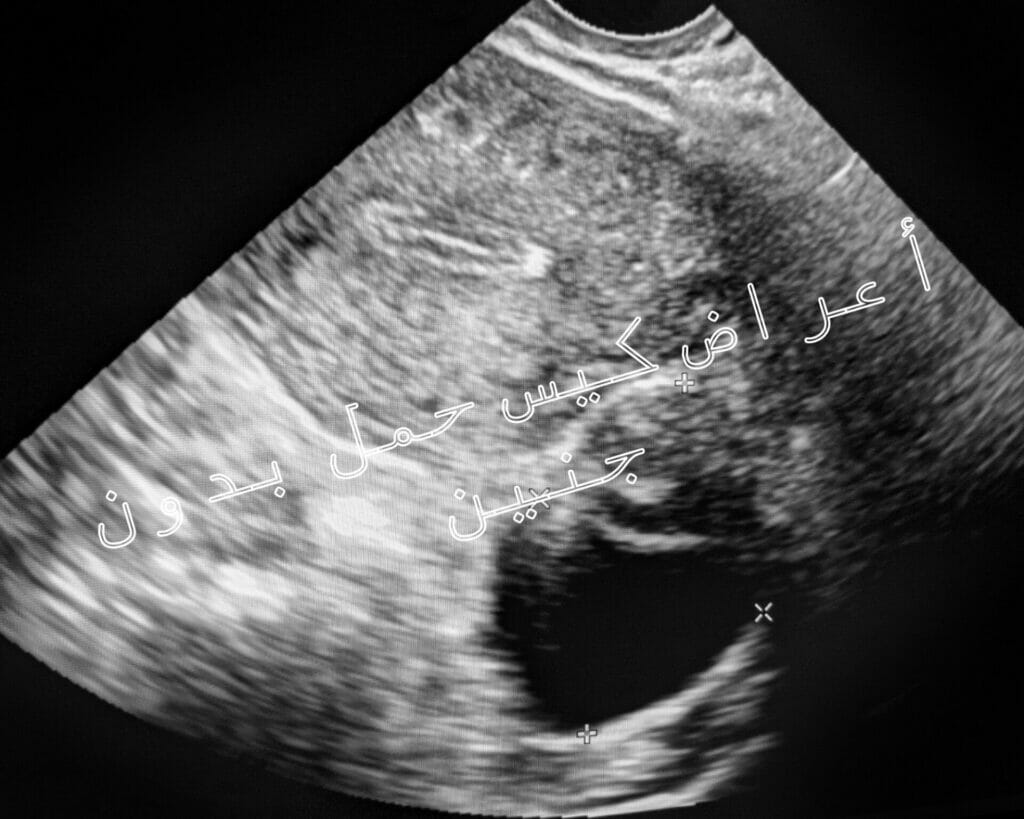

أعراض كيس حمل بدون جنين

تتعرض بعض السيدات لتكوين كيس الحمل بدون وجود الحنين بداخله ويحدث ذلك نتيجة انغراس البويضة الملقحة بجدار الرحم لتبقى كما هي ولا يتم تطويرها لتصبح حنين وهو ما يسمى بكيس حمل بدون جنين وقد يعرف أيضًا باسم الحمل غير المضغي وفي المعتاد يحدث في وقت مبكر حتى أن المرأة قد لا تشعر به ولا تعلم بحملها.

يظهر للحمل بكيس دون الجنين أعراض تتشابه تمامًا مع أعراض الحمل الحقيقي وهي تتمثل فيما يأتي:

- وجود ألم شديد في منطقة الثدي.

- الحصول على النتيجة الإيجابية من اختبار الحمل.

- تأخر في موعد نزول الدورة الشهرية.

بعد سقوط الحمل عشرون أسبوع تظهر على المرأة علامات الإجهاض وهي سقوط كيس الحمل الفارغ مع وجود افرازات بنية تنزل من منطقة المهبل والشعور بآلام شديدة وتشنجات في منطقة أسفل البطن كما أن ألم الثديين يختفي تمامًا ويجب العلم بأن جميع السيدات اللاتي تعرضن للإجهاض بكيس حمل فارغ تمكنوا فيما بعد من الحمل والإنجاب بشكل طبيعي.